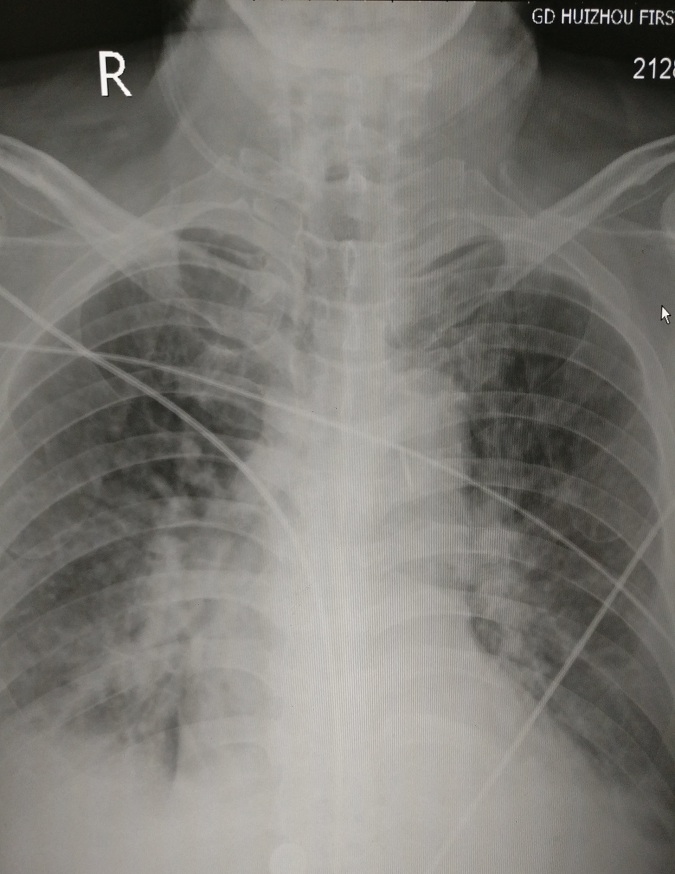

(2)肺泡性肺水肿:经常与间质性肺水肿同在,以“蝶翼状”片状模糊影为典型改变,主要见于急性左心衰竭和尿毒症。见图11。

图11 双侧肺门影增大,肺门旁“蝶翼状”模糊影